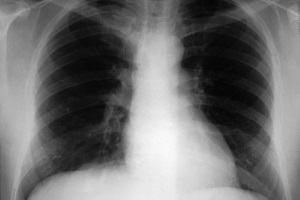

- негоспітальній пневмонії, спричиненій Haemophilusinjluenzaeабо Streptococusрпеитопіае ;

Негоспітальна пневмонія |

10 днів |

800 мг |